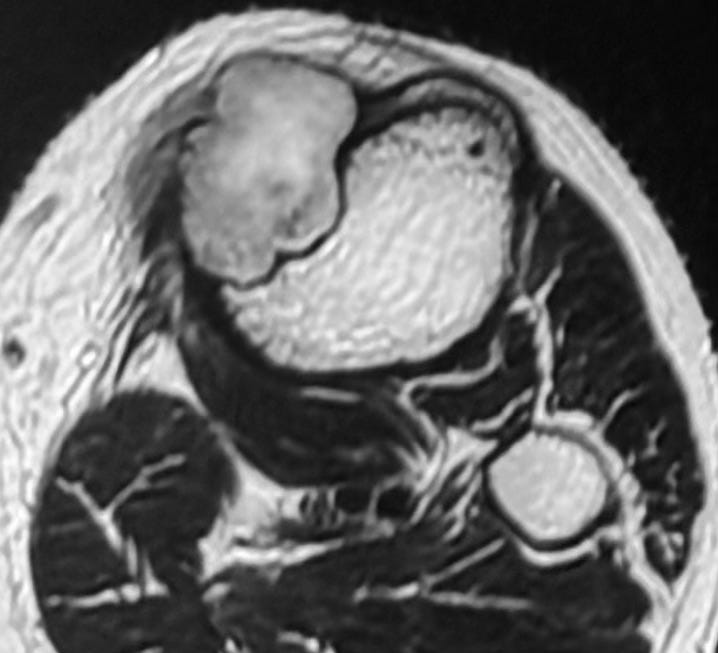

MRI shows marrow edema - this is now a “benign aggressive” lesion.

The lesion is partly T2 dark and shows a lamellated pattern of enhancement and is eccentric juxtamedullary.

The findings are characteristic of chondromyxoid fibroma.